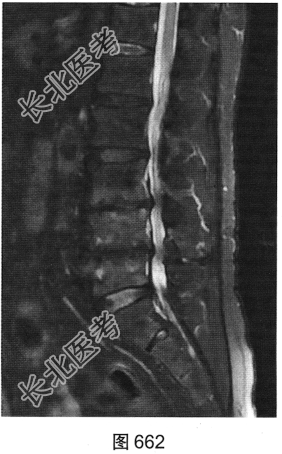

- 多项选择题3.[提示]患者行腰椎MRI检查,如图660~图663所示。患者MRI的T2压脂像上, 部分椎体上、下缘高信号提示( )

A、椎体感染所致的骨髓水肿

B、肿瘤侵蚀破坏

C、椎体轻度压缩骨折

D、脊椎结核

E、退变所致的终板炎

F、椎体脂肪化

- 多项选择题4.综合X线、CT和MRI图像,该患者有以下哪些腰椎退变征象( )

A、终板炎

B、腰椎间盘突出

C、许莫结节

D、黄韧带肥厚

E、腰椎管狭窄

F、腰椎间盘脱出,髓核游离